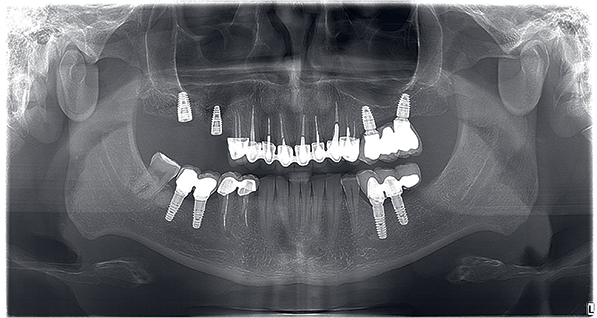

Opšta bolnica BelMedik: originalni ortopan bolesnika koji je, od 2011. do 2019. godine polomio gotovo sve zube i stavio nove implante, koje sada štiti akrilnim umetkom (slika sa dopuštenjem bolesnika). |

Škripanje zubima (Bruxismus)